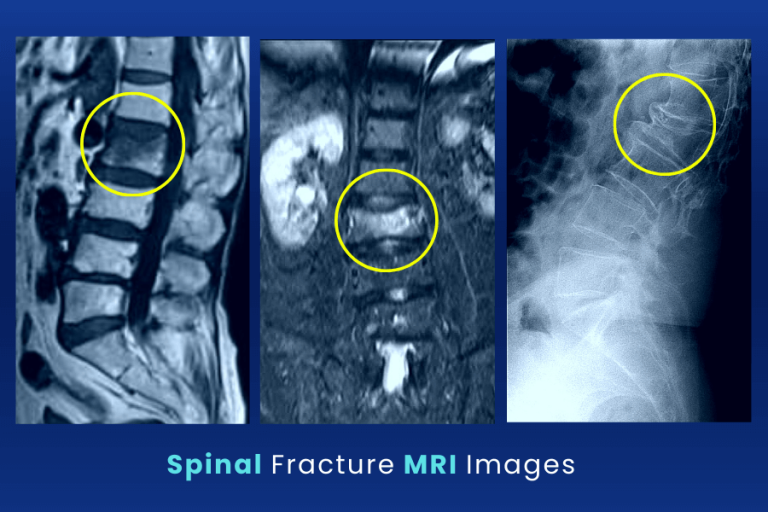

Spinal fractures Classified by mechanism UW Emergency Radiology Can A Fractured Spine Heal Itself  Compression fracture treatments can be surgical or nonsurgical, depending on the severity of the injury. If a patient moves too much during this long recovery period, the. A spinal fracture takes between six and 12 weeks to heal. But the pain usually improves. md describes ways to relieve pain and heal spinal compression fractures without surgery, including physical therapy,. Healing. Can A Fractured Spine Heal Itself.